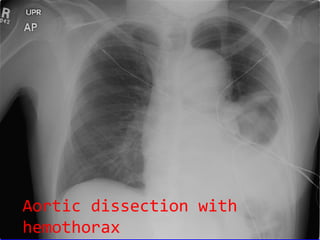

Aortic dissection with hemothorax

Aortic dissection